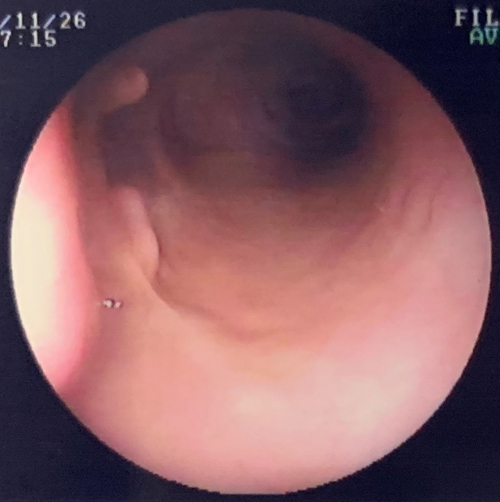

内視鏡を用いることで鼻腔、口腔、咽喉頭、食道、胃、小腸、大腸の炎症や腫瘍病変を発見することができます。

内視鏡検査ではレントゲン、エコー検査では映らない病変をみつけることができたり、炎症や出血している場所などを正しく診断することができます。

また、手術のようにおなかを開けずに、食道や胃腸などを観察できます。その際に小さな異物であれば摘出することもでき、また、ポリープなどの病変が存在する場合は、鉗子を用いて組織を採材し、病理検査をすることで診断が可能になります。